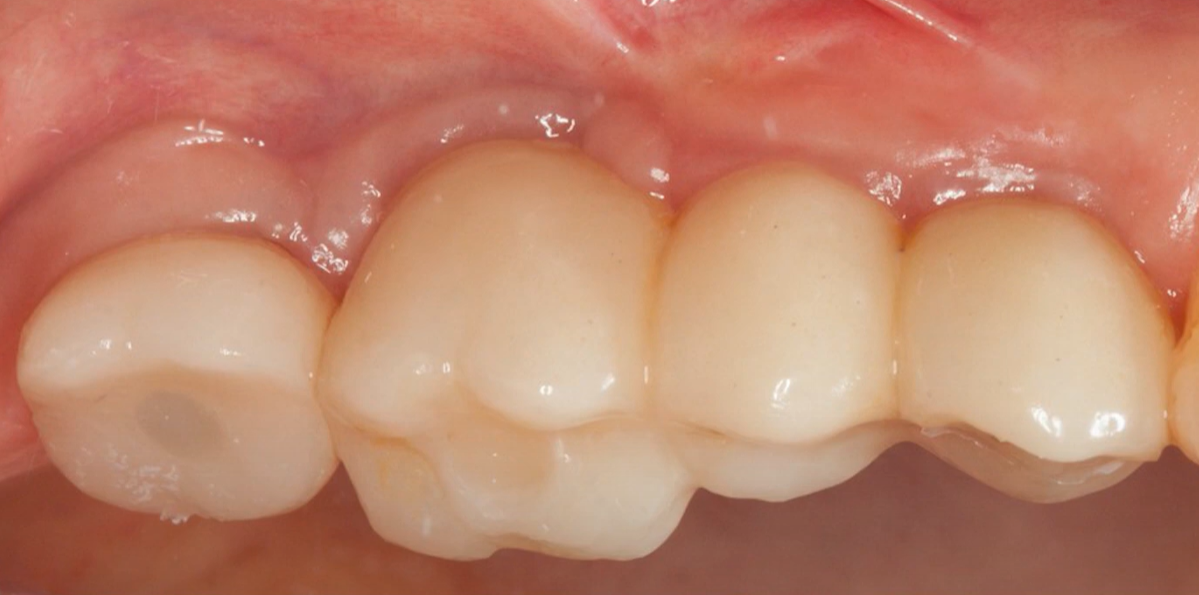

The patient returned for a follow-up examination one year later, in September 2021. The gingiva was healthy, with no signs of recession or inflammation.

A photo of the restoration one year after the final version was installed – a bridge + single crown: the soft tissues are healthy. YouTube/ Implantarium/ Rauf Aliyev

The follow-up radiograph also showed that everything was all right. The bone tissue around the implants was even in better condition after a year.

Control radiograph 12 months after restoring the previously mobile implant. YouTube/ Implantarium/ Rauf Aliyev